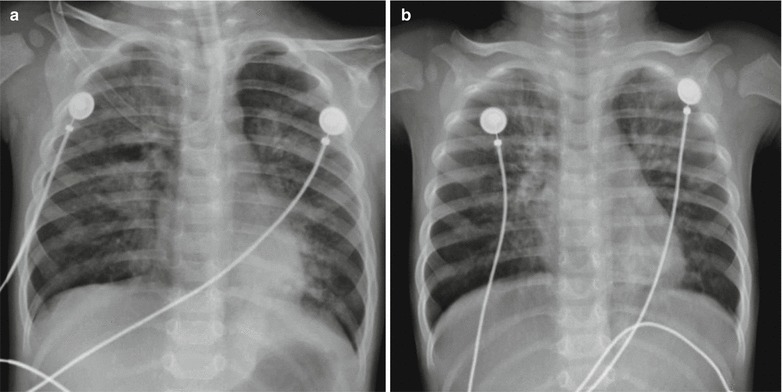

Fig. 23.11.

Pediatric measles complicated by pneumonia. (a) X-ray demonstrates enhanced and blurry pulmonary markings in both lungs and patches of shadows in both lungs, especially in the right lung. (b) By reexamination after the treatment for 4 days, the lesions are demonstrated to be absorbed and improved

Fig. 23.12.

Pediatric measles complicated by pneumonia. (a) X-ray demonstrates enhanced pulmonary markings in both lungs, flakes, and cotton wool-like shadows at the medial part of the right middle and upper lung fields. (b) By reexamination after treatment for 16 days, the lesions at the lungs are demonstrated to be absorbed and improved